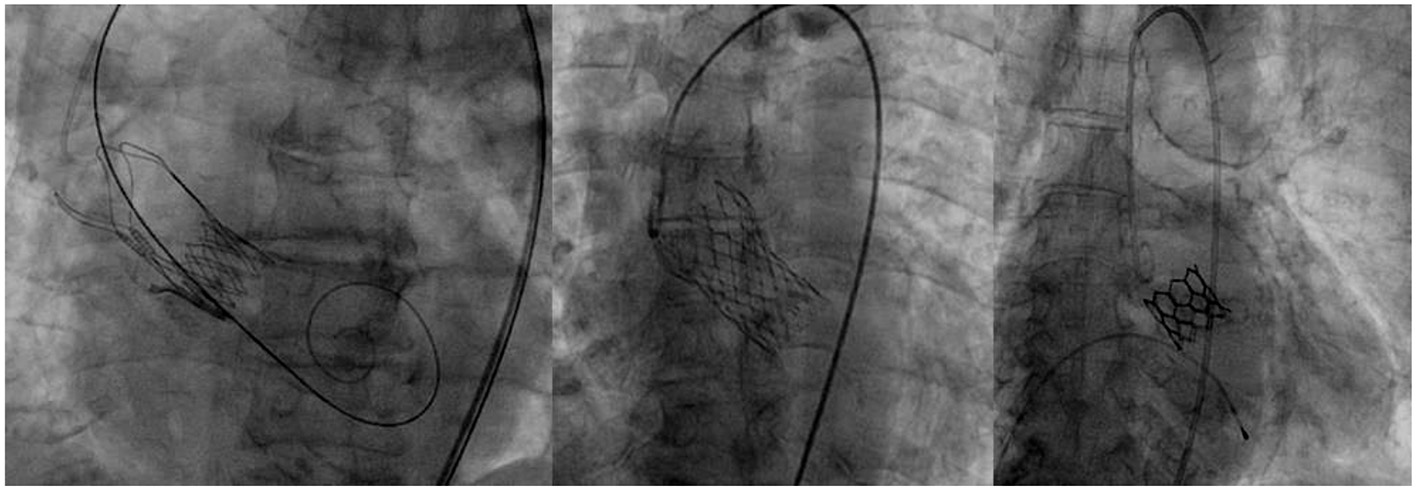

Valves were selected according to each patient's characteristics among the following self-expandable (Evolut R, Medtronic and Acurate Neo, Boston Scientific) or balloon expandable ones (Myval, Meril) (Figure 1). These three devices were used for starting the program, because the TAVI program was operating during the peak of the Covid pandemic, when available valves from one manufacturer were limited. It was also agreed that it would be best to allow a sort of variety of devices in order to match different patient profiles. The choice of valve type was made by the Institute's Structural Heart Team, in accordance with the patient's native aortic valve, size and calcification of ilio-femoral vessels as well as the need for alternative access. Criteria to use either the self-expandable or balloon type was based on criteria set by the patient's health and cardiovascular history. Balloon expandable valves were used in those who had severe calcifications which might lead to valve leakage, as well as in those showing a high risk for permanent pacemaker implantation. In addition, in those patients who presented with severe coronary artery disease that might lead to PCI in the future, balloon type valve was the preferred choice. Due to their supra-annular leaflets, self-expandable valves were used in patients who had small annuli to ensure optimal hemodynamics after implantation. Moreover, in those who were at high-risk for annular rupture, self-expandable valve was used. In cases where there were no limitations set by the patient's characteristics, it was left to the individual operator to use their best judgment to choose the most appropriate valve.

Figure 1

Acurate Neo, Boston Scientific; Evolut R, Medtronic; and Myval, Meril.